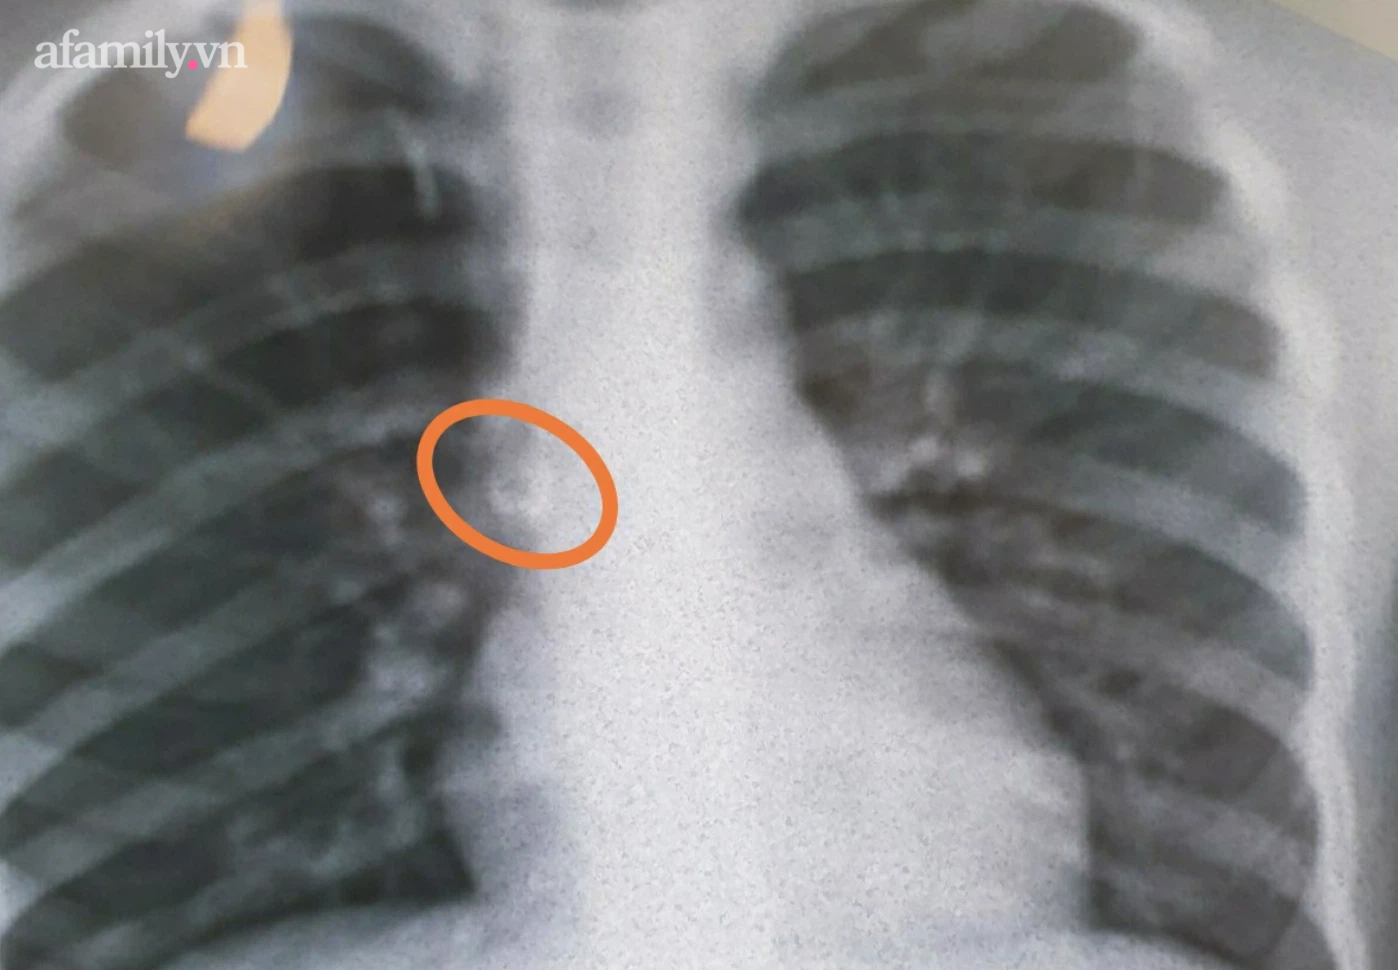

Sáng 5/10, người thân phát hiện ông trong tình trạng kích thích vật vã, muốn tự tử. Gia đình đã nhanh chóng đưa đến bệnh viện cấp cứu. Lúc này người đàn ông có dấu hiệu lơ mơ, các bác sĩ cấp cứu hồi sức, cho thở oxy mask, sinh hiệu ổn định. Trong thời gian theo dõi sức khỏe, bệnh nhân thường xuyên bị đau bụng. Hình ảnh chụp X-quang cho thấy dạ dày bệnh nhân chứa đầy những mẫu hình dạng như răng người, có cái còn cả chân răng sắc nhọn.

Kíp nội soi gắp ra khỏi dạ dày bệnh nhân 7 chiếc răng cùng nhiều dị vật khác. Hiện, bệnh nhân được tiếp tục theo dõi sức khỏe và điều trị trầm cảm.